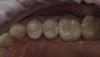

Art 7 Опубликовано 19 декабря, 2012 Автор Поделиться Опубликовано 19 декабря, 2012 стояли коронки на зубах 2,4 и 2,6 контактных пунктов не было,были большие проблемы с сосочками,фото до нет. снял коронки,пародонтология с косточкой,сосочки ушли. выждали 1,5 месяца на временных,временные были блоком. сейчас в ожидании их созревания.не думаю что произойдёт чуда между клыком и четвёркой и 2,6 и 2,7 без изготовления винира или коронки на клык,и коронки на 2,7. но пока пациент не готов на эти манипуляции. ситуацию исправили,сосочки между коронками обязательно будут,будет и фото.хотя могу ошибаться и между клыком и четвёркой и 2,6 и 2,7 сосочки всё таки будутда снимали оттиски с брекетами Ссылка на комментарий